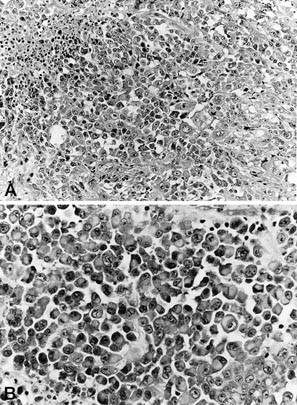

Histologically, 12 tumors (60%) were classified as the large-cell subtype, 6 (30%) as the conventional subtype, and 2 (10%) as the angiomatoid subtype (Table 3). The large-cell epithelioid sarcomas were characterized by sheets of large, rounded polygonal or short spindle cells with enlarged vesicular nuclei, prominent, central single nucleoli and abundant amphophilic cytoplasm (Fig. 2). Rhabdoid cells containing intracytoplasmic, paranuclear hyaline inclusions were abundant in 10 tumors of the large-cell subtype, in three tumors of the conventional subtype, and in one of the angiomatoid subtype. Conventional epithelioid sarcomas displayed nodules of a mixture of atypical spindle and epithelioid cells bordering central areas of hyalinization and necrosis (Fig. 3). Angiomatoid tumors had cystic, blood-filled pseudovascular spaces bordered by epithelioid and spindle cells, similar to those seen in typical cases (Fig. 4).